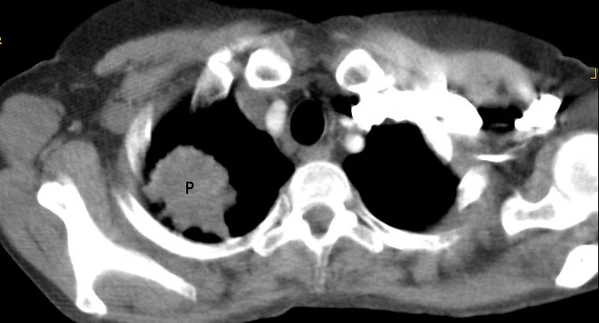

Рак верхушки лёгкого с синдромом Панкоста

Опухоль Панкоста или опухоль верхней борозды лёгкого (это название чаще употребляется в англоязычной литературе) — рак первого (верхушечного) сегмента лёгкого с синдромом Панкоста.